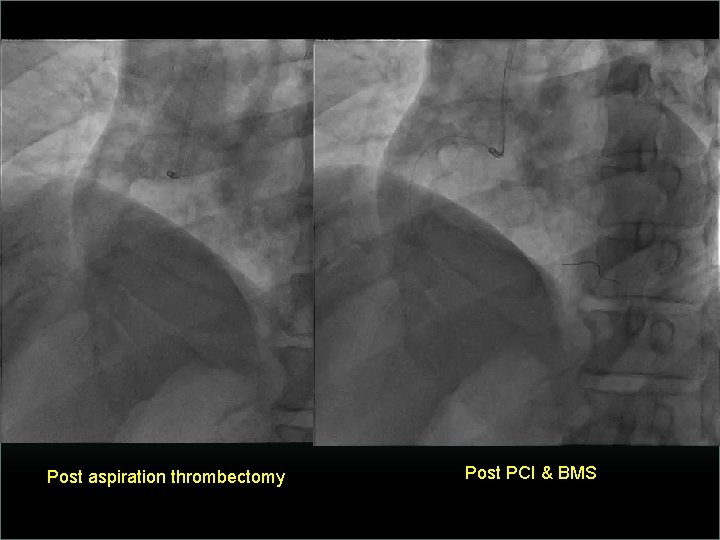

Transradial Interventions Difficult Anatomic Substrate Challenges and Solutions